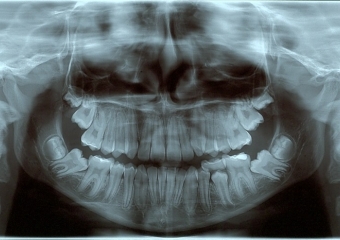

Rx Panorâmico Inicial - Clínica Cliniface

Rx Panorâmico Inicial